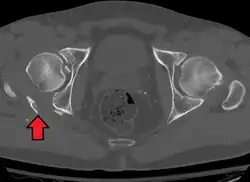

Axial CT image (viewed on bone windows) of a complex comminuted left acetabular fracture involving both anterior and posterior columns. -

Posterior column and wall fracture as seen on 3D CT -